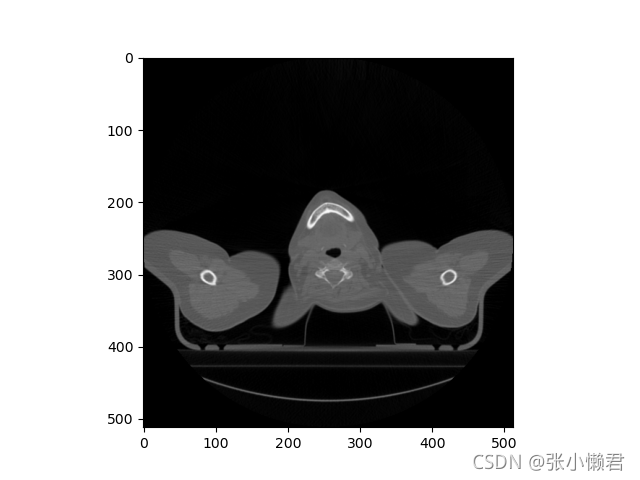

#运行结果:(512,512)还有下图